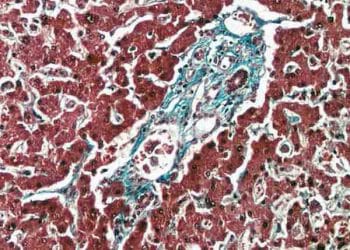

Waterhouse-Friderichsen Sendromu, insanlarda ve septisemik buzağılarda, ateş, böbrek üstü bezinde deride ve müköz zarlarda peteşiyal kanama siyanoz ve peteşiyal kanamalarla...